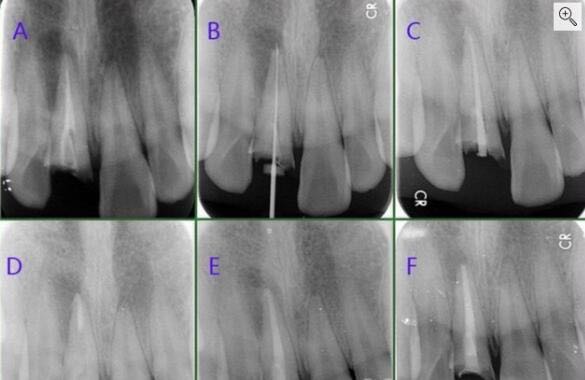

检查及结果:11残根,周围牙龈红肿,探(-),叩(++),冷热诊(-),松(0度) 辅助检查:X线示11根尖暗影较大,根管内见充填物 CT示11根尖唇侧骨板吸收,报告11根尖囊肿

诊断:11根尖囊肿 治疗方案:11试行根管再治疗+根尖手术 治疗过程:橡皮帐隔湿,显微镜下去除11根管内充填物,镍钛器械预备至F3,根管消毒。试尖发现11根管粗大,MTA充填根管下段4.5mm,6小时后热牙胶充填根管上段后行根尖手术,待患者伤口愈合后,制作临时修复体改善患者美观。嘱定期复查,3个 月后11根尖暗影明显减小,